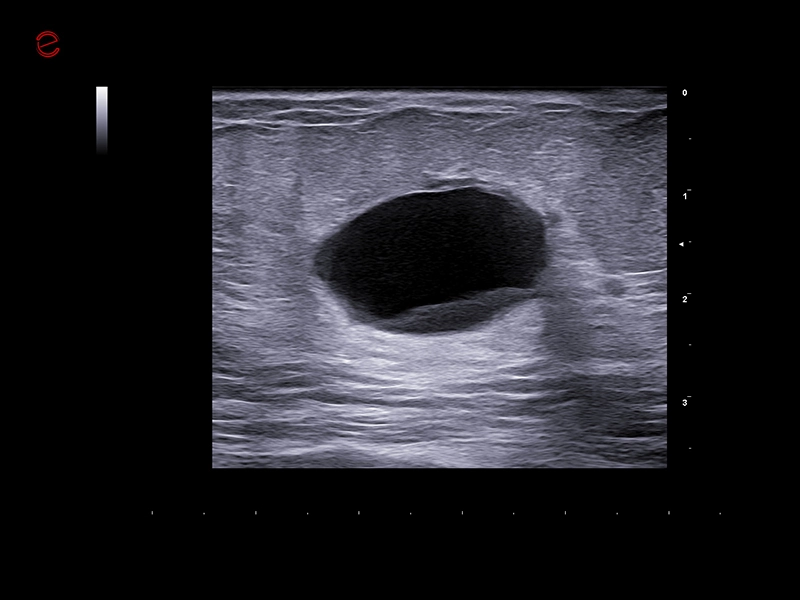

MyLab™C25 - Breast lesion

MyLab™C25 - Breast lesion